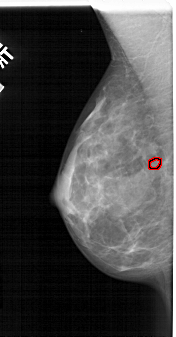

FILE: A_1841_1.LEFT_MLO.OVERLAY TOTAL_ABNORMALITIES 1 ABNORMALITY 1 LESION_TYPE CALCIFICATION TYPE PLEOMORPHIC DISTRIBUTION CLUSTERED ASSESSMENT 4 SUBTLETY 1 PATHOLOGY BENIGN TOTAL_OUTLINES 1 BOUNDARY |

FILE: A_1841_1.LEFT_CC.OVERLAY TOTAL_ABNORMALITIES 1 ABNORMALITY 1 LESION_TYPE CALCIFICATION TYPE PLEOMORPHIC DISTRIBUTION CLUSTERED ASSESSMENT 4 SUBTLETY 1 PATHOLOGY BENIGN TOTAL_OUTLINES 1 BOUNDARY |